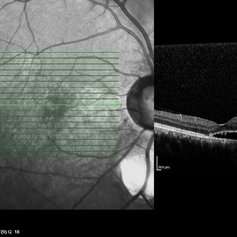

Best Disease Best DiseaseMar 9 2013 by Hamid Ahmadieh, MD OCT of the right eye of a 49-year-old man with decreased VA due to advanced Best disease. Photographer: Soodabeh Fooladin, Negah Eye Center, Tehran Imaging device: Heidelberg Spectralis Condition/keywords: Best disease, optical coherence tomography (OCT)

Best Disease Best DiseaseMar 9 2013 by Hamid Ahmadieh, MD OCT of the left eye of a 49-year-old man with decreased VA due to advanced Best disease. Photographer: Soodabeh Fooladin, Negah Eye Center, Tehran Imaging device: Heidelberg Spectralis Condition/keywords: Best disease, optical coherence tomography (OCT)